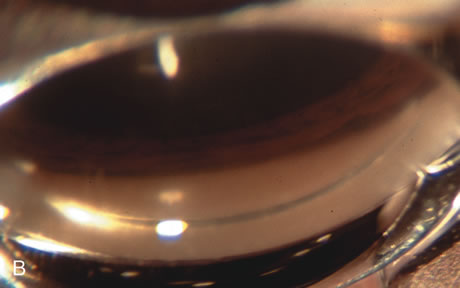

Fig. 3. Partial bleb failure following clear corneal phacoemulsification with foldable IOL. A. Preoperative bleb appearance prior to temporal lens extraction. Preoperative IOP was 12 mm Hg on no antiglaucoma medications. Time from 5-FU trabeculectomy surgery to lens extraction was one year. B. Bleb appearance 2 months after clear corneal cataract surgery with topical anesthesia. Following lens extraction, increased vascularity was noted along with decreased size of the filtering bleb. IOP increased to 20 mm Hg as early as 2 weeks after surgery, necessitating topical antiglaucoma therapy. C. High magnification view of bleb before lens extraction demonstrates diffuse pale bleb. D. High magnification view of bleb 2 months after surgery. There are vessels surrounding the nasal side of the bleb and the overall bleb size is smaller.

Fig. 1. The anatomic advantage of small incision cataract surgery for the glaucoma patient. A. Long-term bleb function with a large cataract incision is difficult to achieve with either ECCE-trabeculectomy or trabeculectomy followed later by ECCE. This bleb failed to form sufficiently when combined with large incision ECCE. The inflammation, bleeding, and long-term wound healing with stimulation of fibroblasts associated with this technique are more likely to cause bleb failure. In addition, the increased iris manipulation necessary to deliver the nucleus and subsequent iris repair adds to the long-term breakdown of the blood aqueous barrier. B and C. Two-site phacotrabeculectomy has the advantage of small incision cataract surgery combined with separate site trabeculectomy. The incision size is one third the size of the standard ECCE. The inflammation is less severe, and cataract wound healing is confined to the temporal area. Visual rehabilitation with phacoemulsification and foldable IOL is much faster. Phacoemulsification allows successful lens extraction even in the unfriendly environment of a smaller pupil compared with ECCE. The trabeculectomy is performed in an entirely different site, well away from the wound healing associated with temporal phacoemulsification. The likelihood of this filter functioning long-term is greater than with ECCE-trabeculectomy. D. The surgeon also has the option of single-site phacotrabeculectomy with foldable IOL. Both the lens extraction and trabeculectomy are performed through one small 3.5-mm limbal incision.